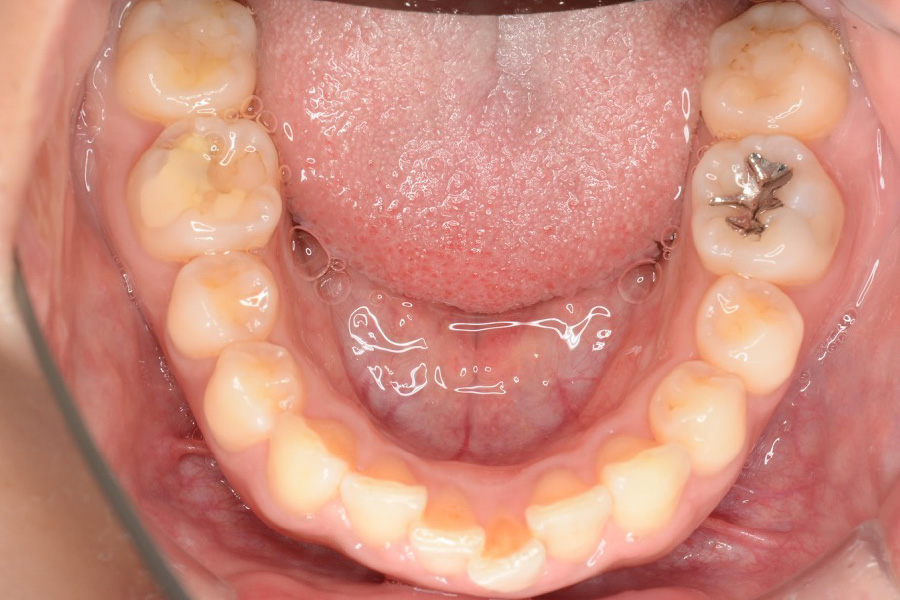

【20代女性】

全体のガタつきを

インビザライン矯正で治療したケース

治療前

主訴 全体のガタつきが気になる

治療内容 インビザライン矯正

非抜歯